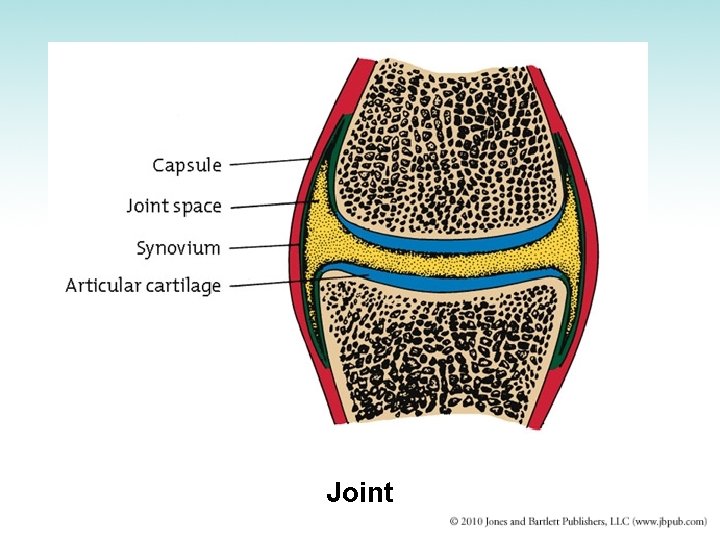

Skeletal System (2 of 2) • Types of cells in bone – Osteoblasts – Osteocytes – Osteoclasts • Strength and thickness of bones depend on activity • Bones of skeleton are connected by joints • Types of joints – Fibrous joint – Cartilaginous joint – Synovial joint

Joint